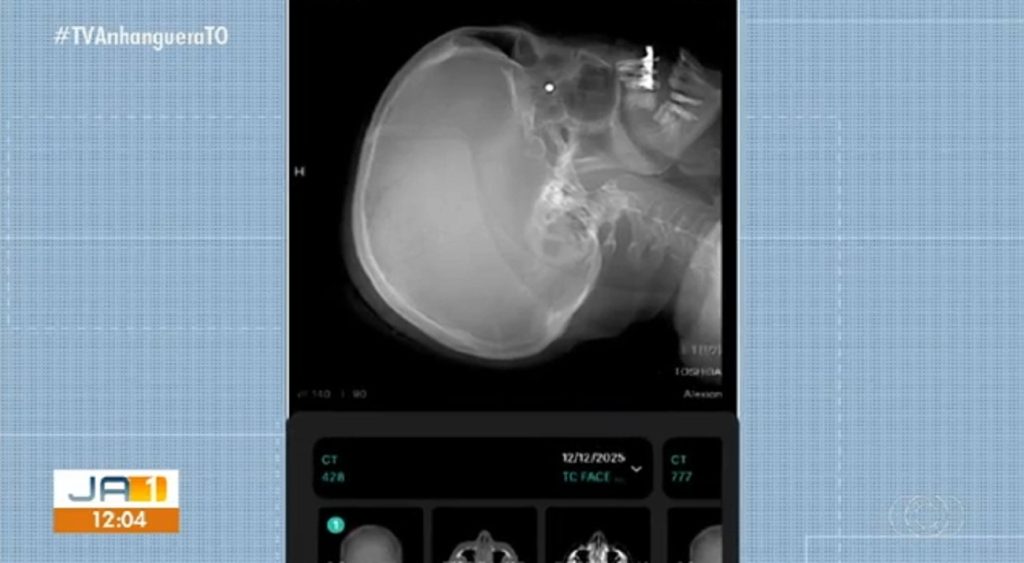

Mulher atingida por tiro em barraca de parque está com chumbinho alojado no olho

A servidora pública Isabel Cristina Rocha, que foi atingida no olho por um chumbinho enquanto passava atrás de uma barraca de tiro, permanece com a bala alojada atrás do globo ocular. O projétil pode não ser retirado, conforme orientação médica. A barraca foi instalada irregularmente na Vila de Natal, no Parque Cesamar, em Palmas.

Exames de raio-X confirmaram que o chumbinho está atrás do globo ocular. Segundo a filha, Agnes Rocha, a mãe passou por quatro oftalmologistas e todos recomendaram não retirar o chumbinho por enquanto. “Graças a Deus ela não está sentindo nenhuma dor desde o momento que ela foi acertada até depois da cirurgia, ela não não sentiu dor na no olho”, contou.

Raio-X mostra projétil atrás do globo ocular de Isabel Cristina Rocha

TV Anhanguera/Reprodução